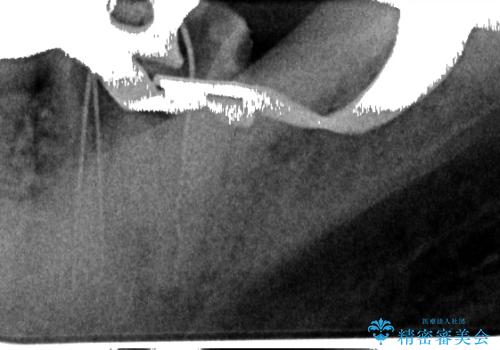

歯根破折の疑いがあり、顕微鏡下で染色して確認したところ破折線は認められませんでした。

そのため再根管治療の適応と判断し、治療を進めていくこととしました。